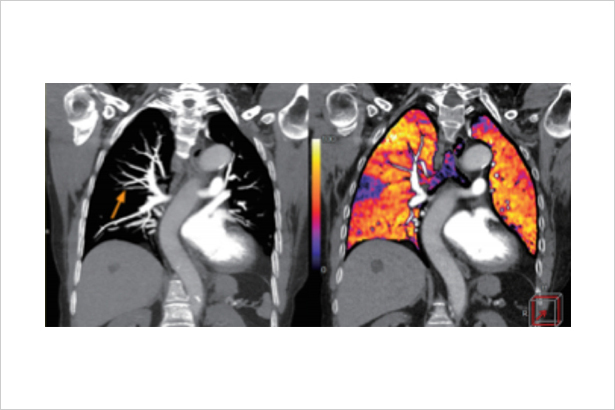

秉承佳能醫療超高端640層CT的AI同步軌道掃描技術與柔性掃描與彩色成像技術,在不增加掃描代價和患者輻射劑量代價的前提下,利用平掃和增強數據進行柔性的器官配準,0鍵式地得到彩色碘圖等有價值的診斷信息,更敏感地發現病灶和淹沒在器官背景的微小血供變化。

在柔性彩色肺部成像下,微小的亞段肺動脈栓塞引起的肺部血流灌注異常被敏感地發現。